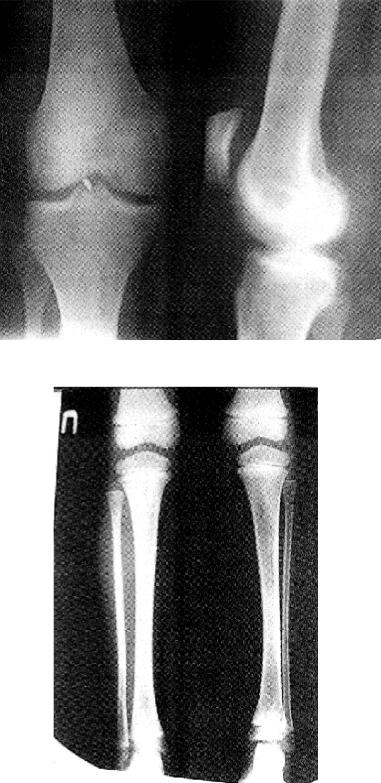

Коленный сустав исследуется в двух проекциях. В прямой проекции хорошо видны ровные контуры мыщелков бедра и большеберцовой кости (рис.6.15). В боковой проекции хорошо различаются овальные контуры мыщелков бедренной кости, тени которых наслаиваются друг на друга. Отчетливо виден надколенник. Рентгеновская суставная щель представлена полосой просветления, более широкой спереди и сзади (рис. 6.15).

Обзорные снимки коленного сустава показаны на рис.6.15.

Рис. 6.15 Обзорная рентгенограмма костей коленного сустава в двух проекциях с законченным ростом костей. Инородное тело в суставной рентгеновской щели.

Рис. 6.16 Обзорная рентгенограмма костей голени и коленного сустава. Нижняя треть бедренной кости ребёнка с незаконченным ростом костей.